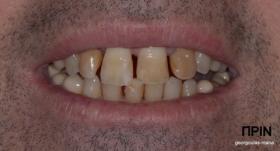

ΠΡΟΣΘΕΤΙΚΗ ΑΠΟΚΑΤΑΣΤΑΣΗ ΣΤΗΝ ΑΝΩ Κ ΚΑΤΩ ΓΝΑΘΟ ΚΑΙ ΤΟΠΟΘΕΤΗΣΗ ΕΜΦΥΤΕΥΜΑΤΩΝ ΜΕ ΚΛΕΙΣΤΗ ΑΝΥΨΩΣΗ ΙΓΜΟΡΕΙΟΥ

Ο ασθενής  προσήλθε στο ιατρείο μας θέλοντας να βελτιώσει την εμφάνιση των πρόσθιων δοντιών του και να αποκαταστήσει την υγεία κ την λειτουργία όλου του στόματος. Πραγματοποιήθηκε περιοδοντική θεραπεία κ ενδοδοντικές θεραπείες (απονευρώσεις) όπου κρίθηκε απαραίτητο και στη συνέχεια τοποθετήθηκαν 3 εμφυτεύματα, 2 δεξιά στις θέσεις του πρώτου κ δεύτερου γομφίου κ 1 αριστερά στη θέση του πρώτου προγομφίου. Κατά την  τοποθέτηση των 2 εμφυτευμάτων της δεξιάς πλευράς, πραγματοποιήθηκε κλειστή ανύψωση ιγμορείου με το σύστημα Piezotome-Intralift , τεχνική που εξασφαλίζει τη μικρότερη δυνατή επέμβαση κ τη μικρότερη μετεγχειρητική ταλαιπωρία (minimally invasive), καθώς κ αυξητικους παράγοντες PRF. Σε όλη τη διάρκεια της θεραπείας  ο ασθενής ήταν καλυμμένος τόσο αισθητικά όσο και λειτουργικά με προσωρινές μεταβατικές αποκαταστάσεις. 4 μήνες μετά την  τοποθέτηση των εμφυτευμάτων κ την οστεοενσωμάτωσή τους, ακολούθησε η τοποθέτηση των μόνιμων αποκαταστάσεων.